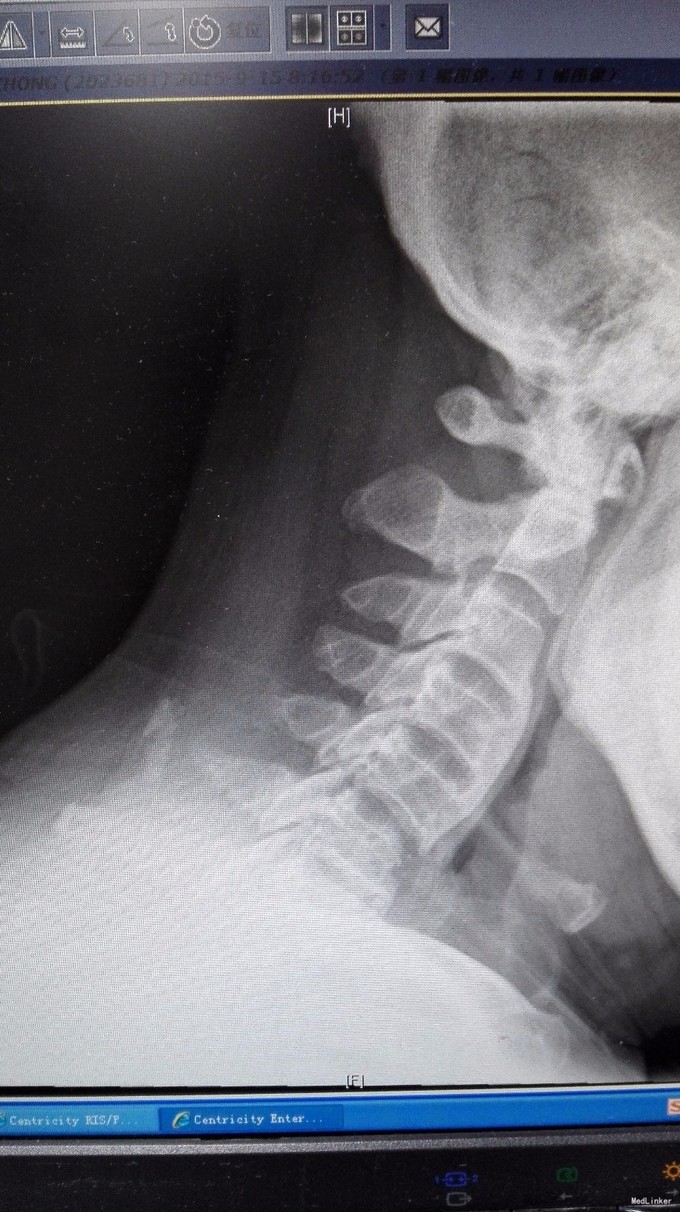

主诉:双手第2、3指尖麻木1年,加重伴双下肢沉重感4月。 病史:1年前出现双手食指、中指指尖麻木,未予以治疗,4月前出现双下肢沉重感,予以腰椎按摩后双下肢症状有所缓解,但双下肢仍有沉重感,右下肢较重,在外院诊治为颈椎病,建议手术治疗,患者拒绝,为求进一步诊治,特来我院就诊,门诊拟混合型颈椎病收入我科住院治疗。

查体:双手麻木感,肱三头肌肌腱反射活跃,左侧髂腰肌4级,臂丛牵拉实验阴性,椎间孔挤压实验阴性。 辅查:CT:C2-7椎间盘突出,继发性椎管狭窄,OPLL,OFL。

诊断:混合型颈椎病(脊髓型+神经根型) 治疗:颈后路3-7单开门椎管扩大成型术(锚定法)